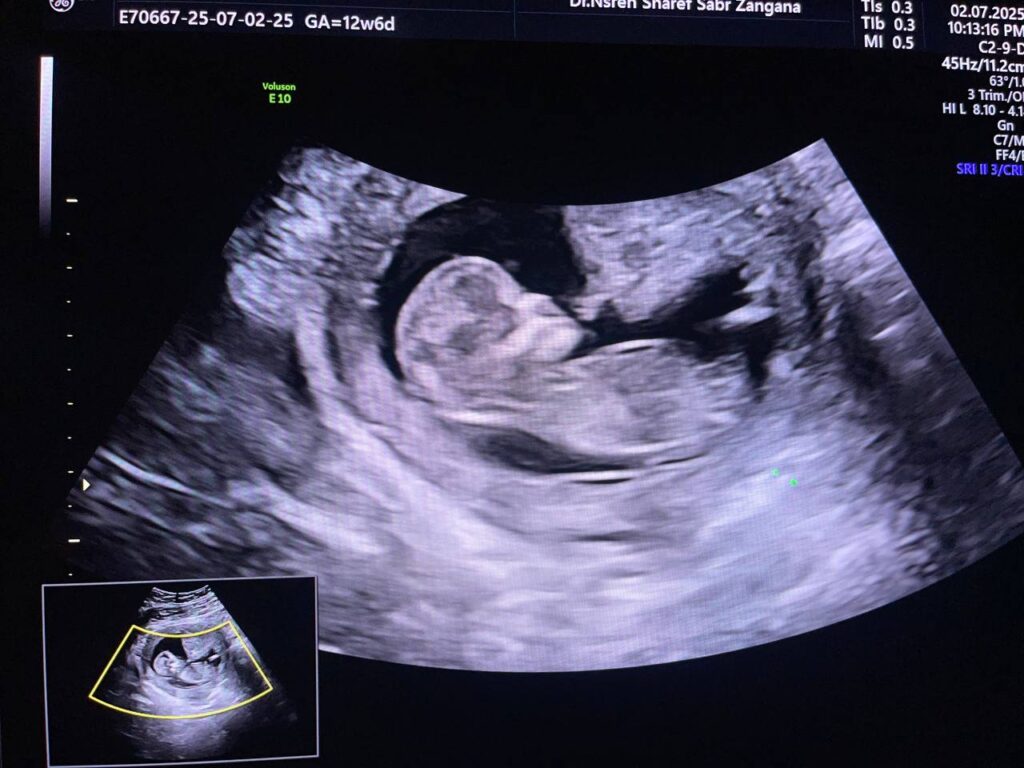

Increase nuchal translucency 7.3mm , mild diffuse skin edema ,Hypoplastic nasal bone, congenital heart disease can not be excluded , please for chromosomal study